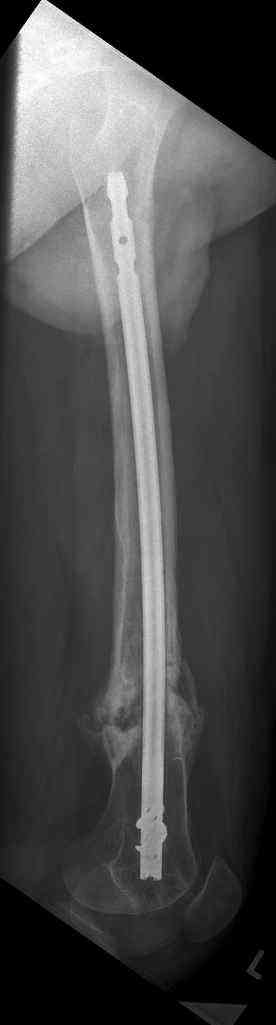

16 yr old boy, high energy motorcycle trauma trauma in July 2005 with:

- distal femoral fracture L

feb 07: retrograde nail + bone graft + BMP

may 07: dynamisation nail

sept 07: locking screw removal (max. dynamisation reached)

nov 07: persistant non-union distal femur; other fractures healed uneventfully.

All with gradual/partial weightbearing etc. Currently 50-100% weight bearing, no pain.

Soft tissues are intact. No smoking or diabetes.CRP <2

What would you do?